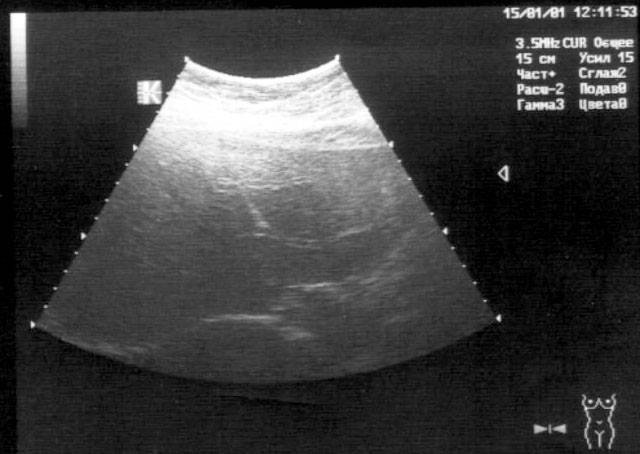

Консультация гастроэнтеролога редко приводит к своевременному выявлению гемангиомы печени, ведь она практически никак не проявляет себя. Обычно доброкачественная сосудистая опухоль печени обнаруживается как случайная находка во время обследования по поводу другой патологии. УЗИ печени и желчного пузыря может выявить в паренхиме округлое образование с четкими контурами, неоднородным содержимым. Те же данные, но гораздо более точные, получают и при МРТ печени и желчевыводящих путей, МСКТ брюшной полости. Убедиться, что выявленная опухоль является гемангиомой печени, позволят ангиография чревного ствола (целиакография), статическая сцинтиграфия печени. Гепатосцинтиграфия используется для дифференцировки злокачественных и доброкачественных новообразований.